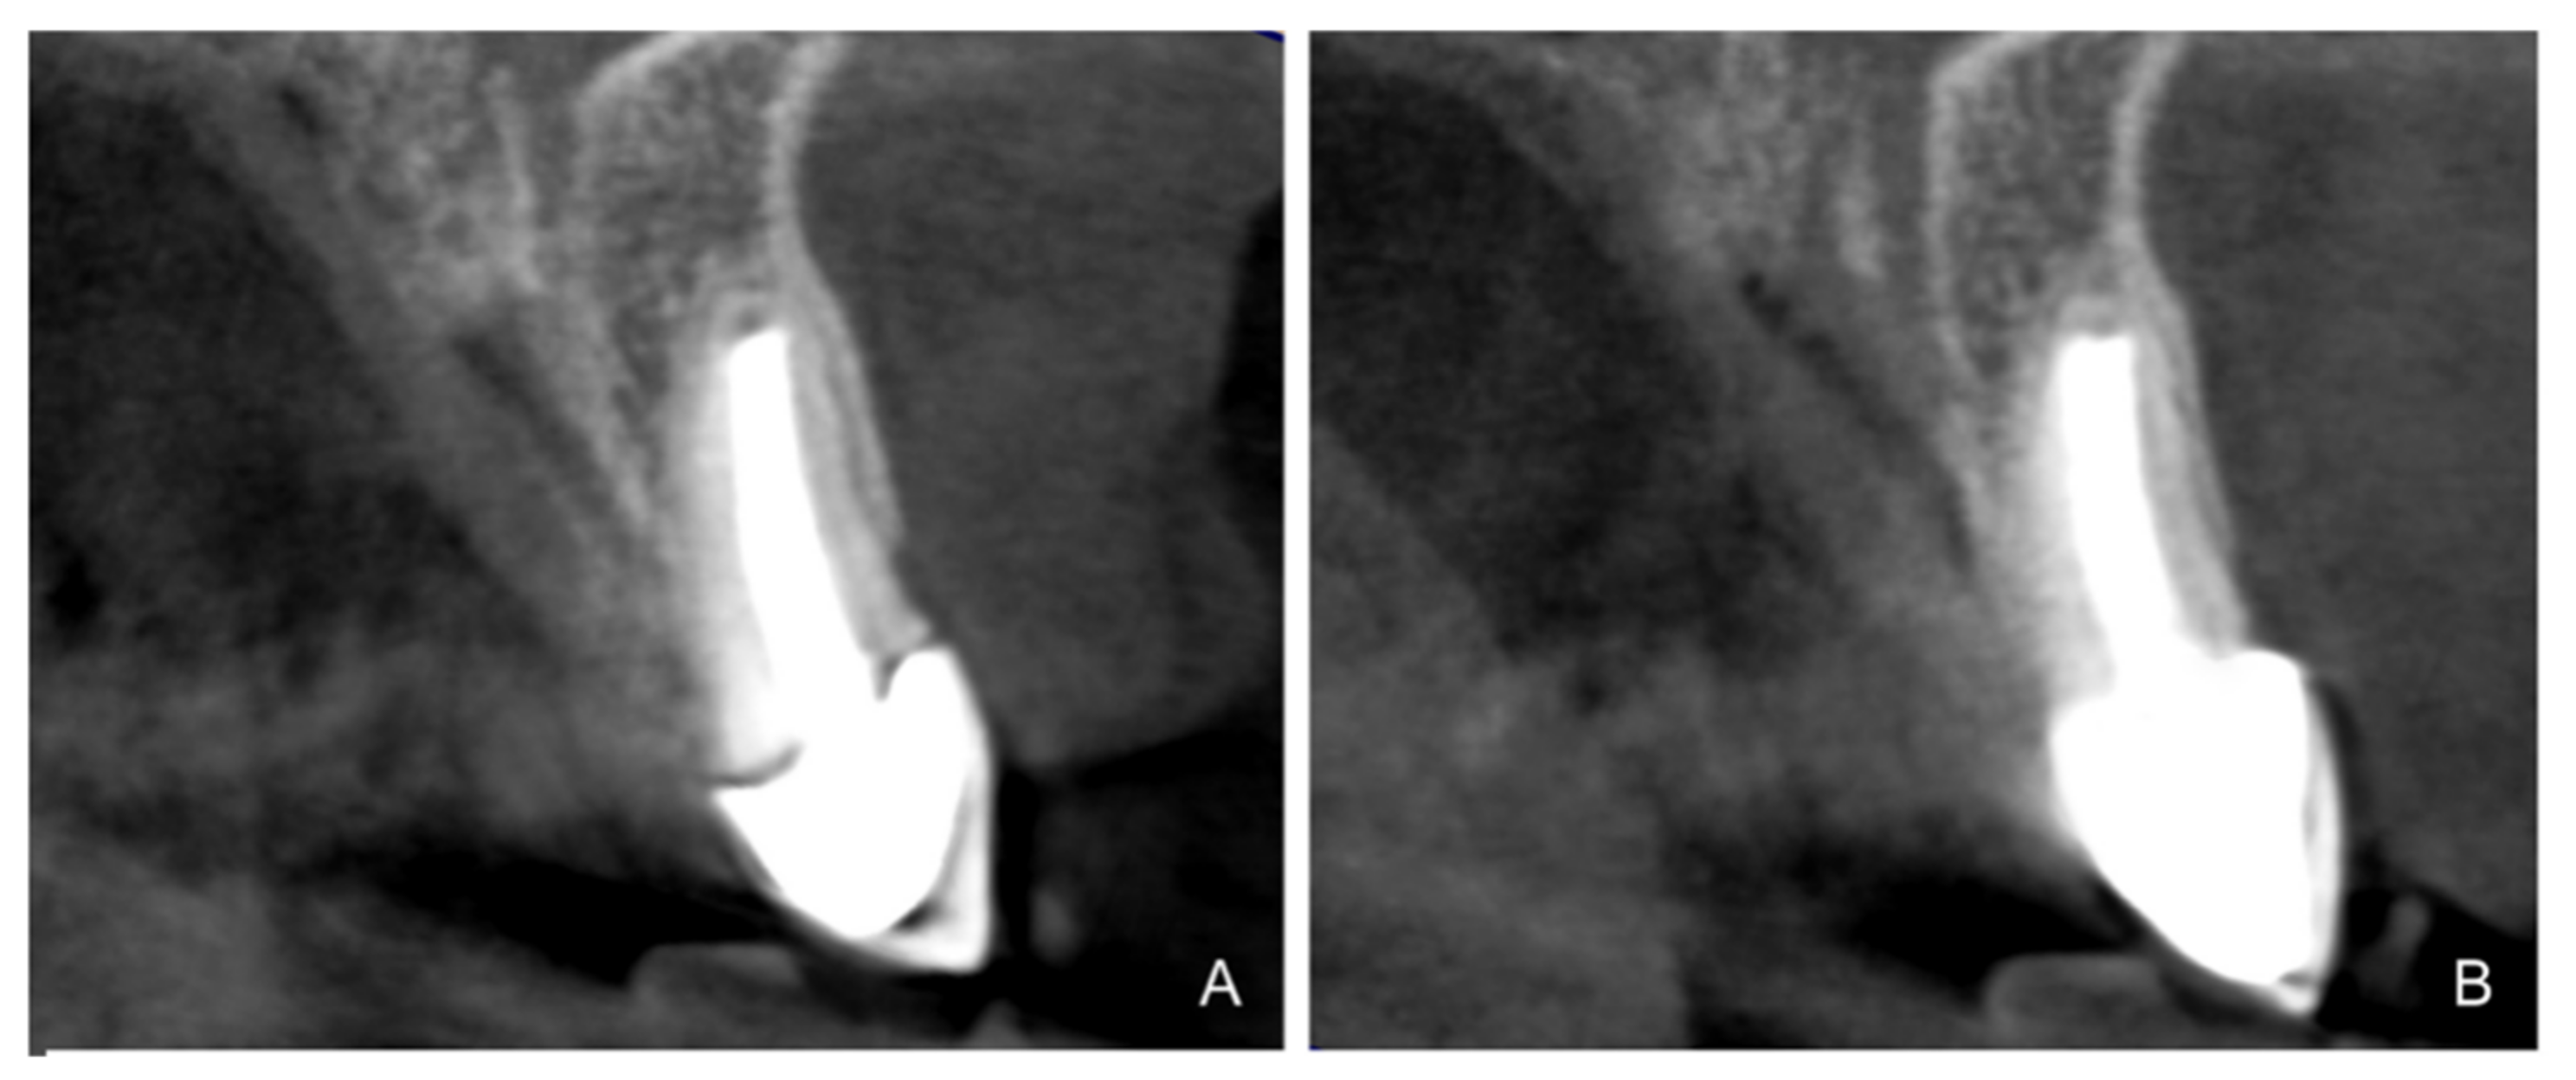

- Agustín-Panadero, R.; Solá-Ruíz, M.F. Vertical preparation for fixed prosthesis rehabilitation in the anterior sector. J. Prosthet. Dent. 2015, 114, 474–478. [Google Scholar] [CrossRef] [PubMed]

- Agustín-Panadero, R.; Serra-Pastor, B.; Fons-Font, A.; Solá-Ruíz, M.F. Prospective Clinical Study of Zirconia Full-coverage Restorations on Teeth Prepared with Biologically Oriented Preparation Technique on Gingival Health: Results After Two-year Follow-up. Oper. Dent. 2018, 43, 482–487. [Google Scholar] [CrossRef] [PubMed]